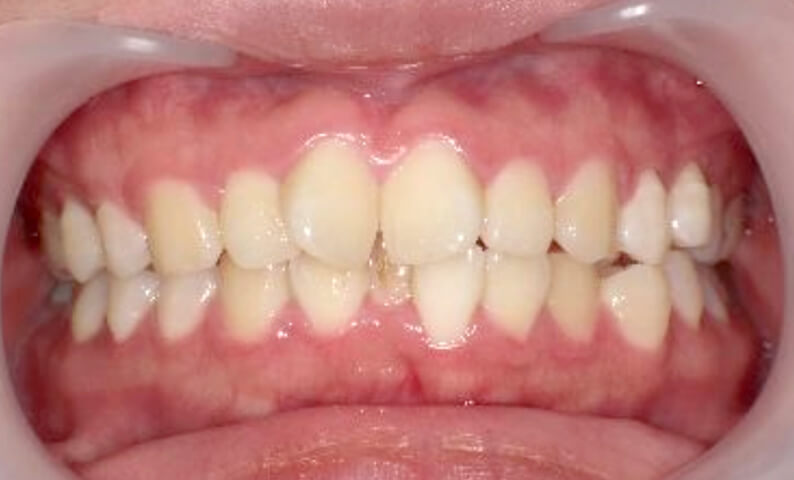

症例_024 上下顎の部分矯正

治療期間:13ヶ月金額:51万円+税女性前歯のガタガタ八重歯

| Before | After |

|---|---|